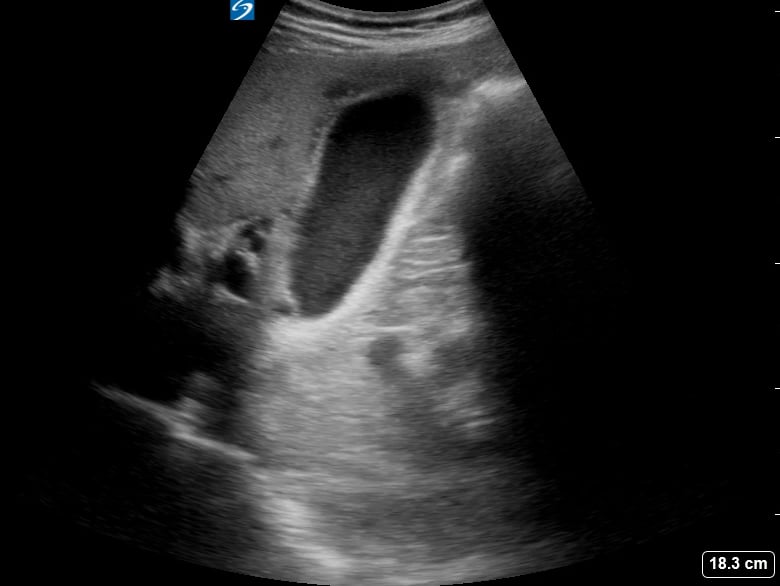

Pericholecystic fluid, in abdominal ultrasound, refers to an abnormal collection of fluid surrounding the gallbladder. Its presence is a key indicator of gallbladder inflammation, commonly seen in acute cholecystitis, a condition causing severe abdominal pain. Sonographers meticulously assess this fluid for its location, amount, and characteristics to aid in accurate diagnosis.

This fluid accumulation is a crucial diagnostic sign for healthcare professionals. Early detection via ultrasound helps guide timely medical intervention and treatment strategies, preventing further complications related to gallbladder disease and improving patient outcomes in abdominal imaging.